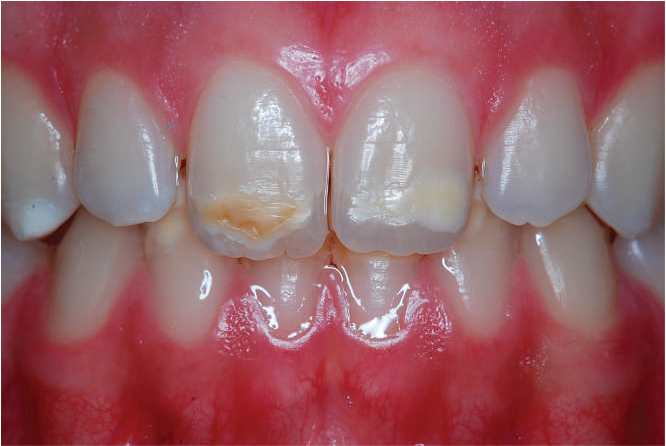

Enamel hypoplasia, characterized by thin, defective, or underdeveloped enamel, poses unique challenges for orthodontic treatment. These patients are more prone to enamel fractures, sensitivity, and an increased risk of caries. Clear aligners, known for their gentler approach compared to traditional braces, can be customized to cater to these patients' needs while minimizing potential risks to their already fragile enamel.

Understanding Enamel Hypoplasia in Orthodontics

Enamel hypoplasia can be congenital or acquired, affecting the structural integrity of the teeth. Key considerations for orthodontic treatment include:

Increased Fragility: Enamel is more prone to wear and fractures during treatment.

Sensitivity: Patients often report heightened sensitivity to thermal, chemical, or mechanical stimuli.

Risk of Decalcification and Caries: The compromised enamel structure makes oral hygiene critical during treatment.